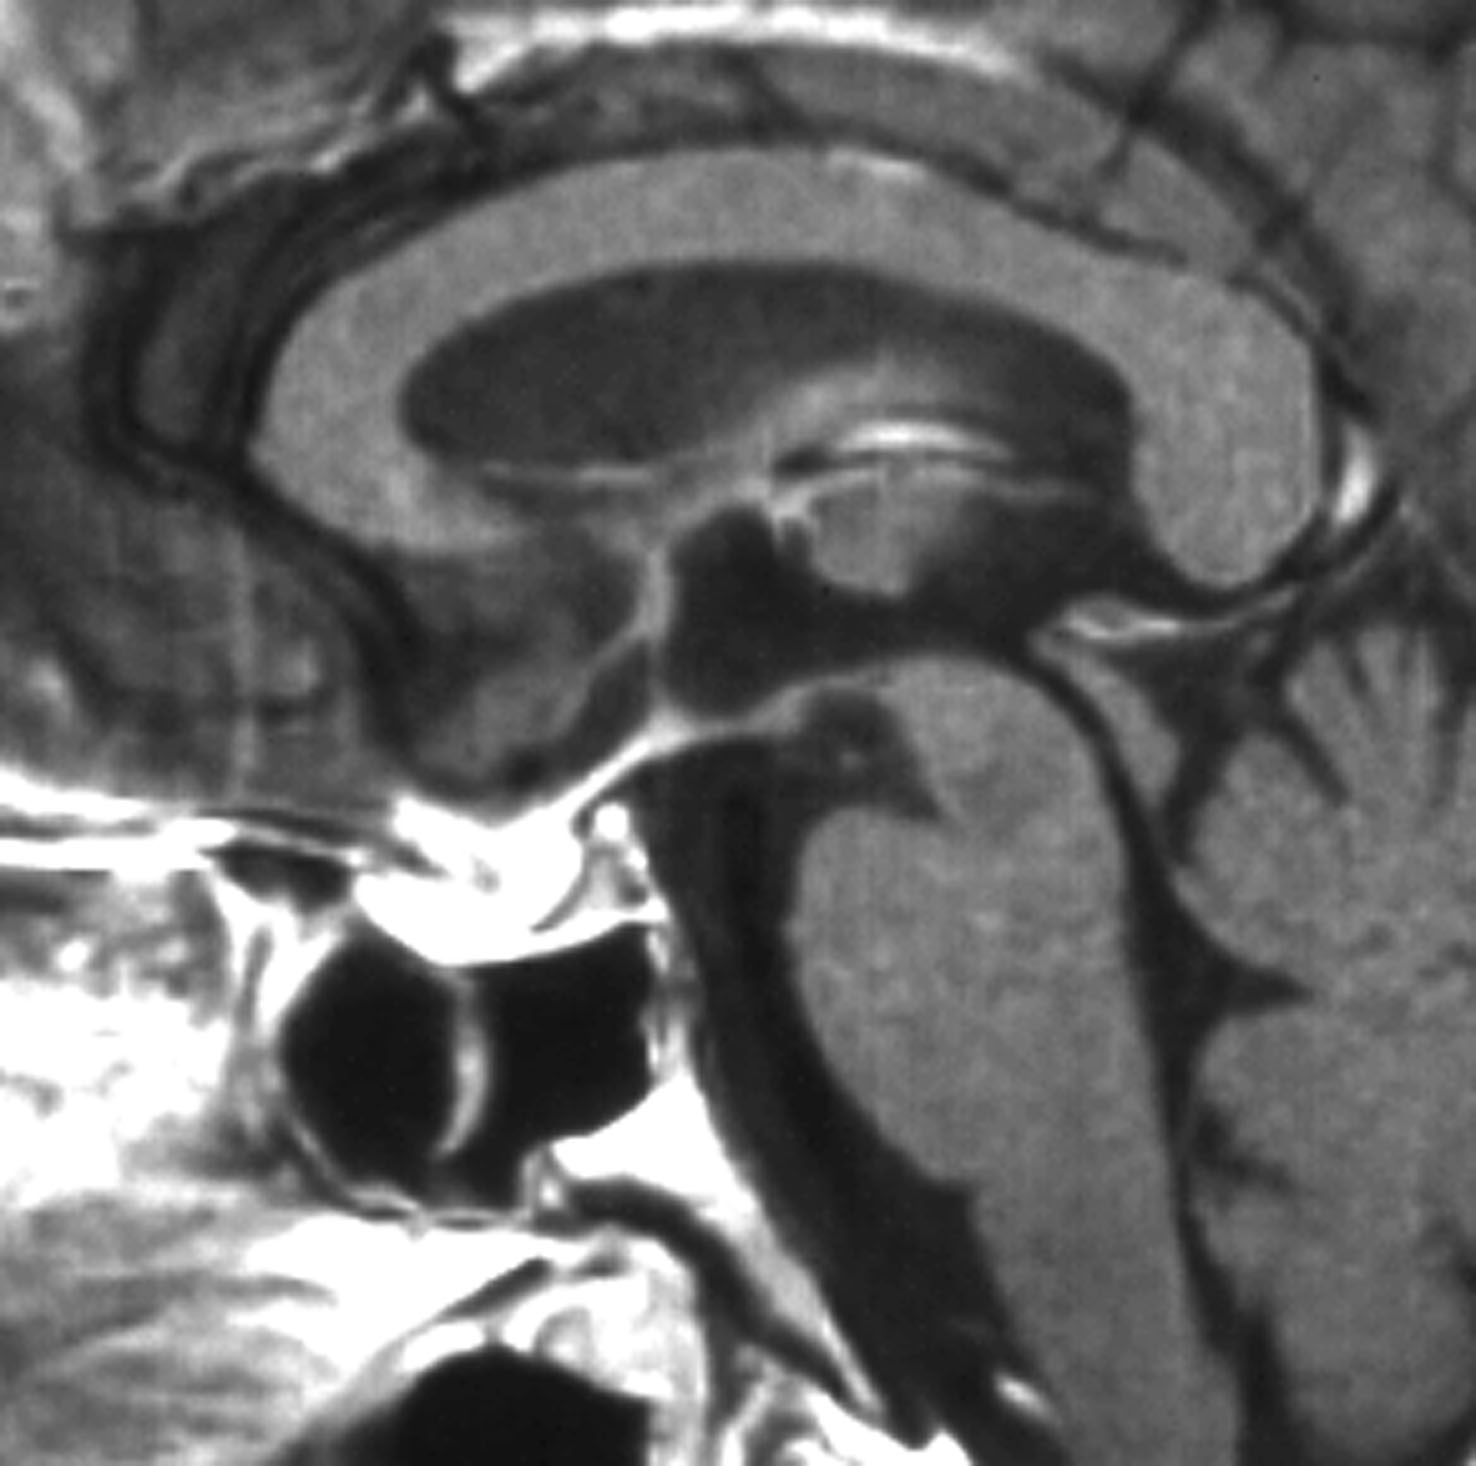

この例は18歳,HCG 0.1mIU/ml,尿崩症で発症しました。神経下垂体ジャーミノーマなので,下垂体前葉のみが残って後葉から視床下部が腫瘍化しています。よくよく見ると松果体にもごく小さな腫瘍があります。右のCISS画像で松果体の腫瘍化が明瞭です。

経鼻生検術で下垂体後葉部分がgerminomaということを確認してからICE (IFO/CDDP/VP-16)を1コース加えて3週間後の画像です。腫瘍は灰白隆起の部分を残してほぼ消失しています。松果体部の腫瘍も消えています。典型的なgerminomaの化学療法反応性を示しています。下垂体前葉機能は正常,尿崩症も少し良くなりました。